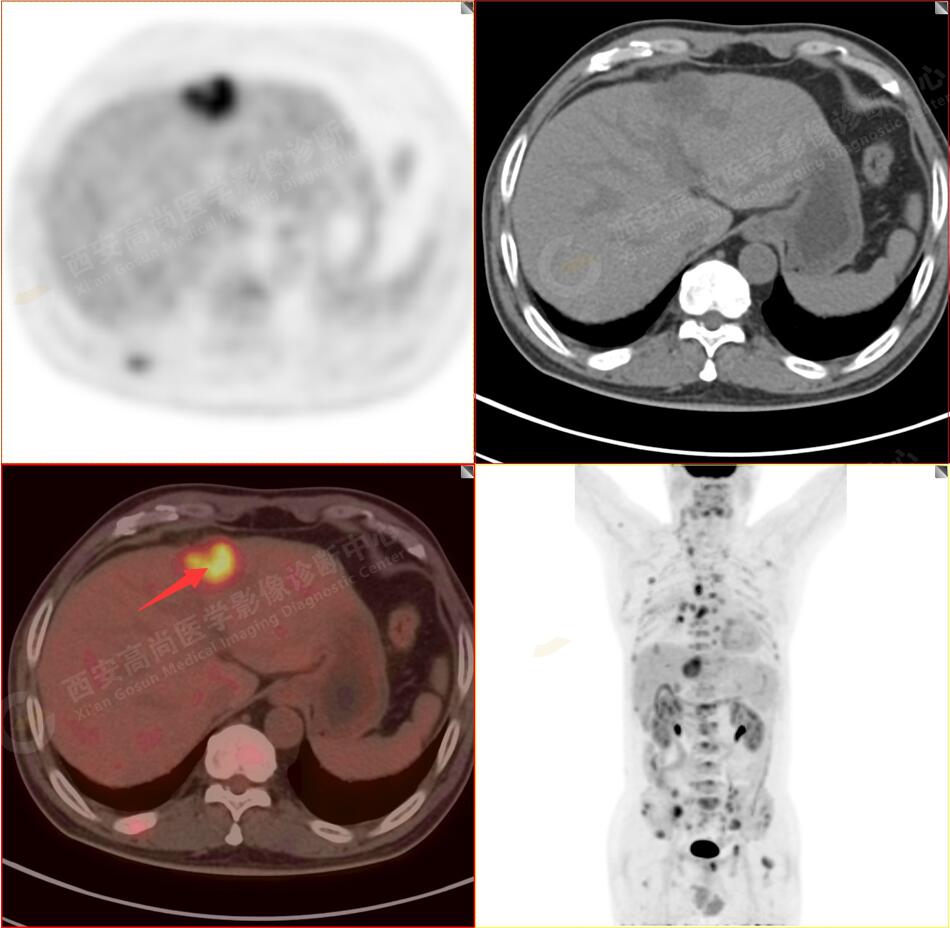

2.以下為全身多發(fā)轉移灶

4.肝S4、8段團塊狀及結節(jié)狀低密度病變,以S4段病變?yōu)橹?,呈不同程度FDG代謝異常增高,考慮為肝多發(fā)轉移。